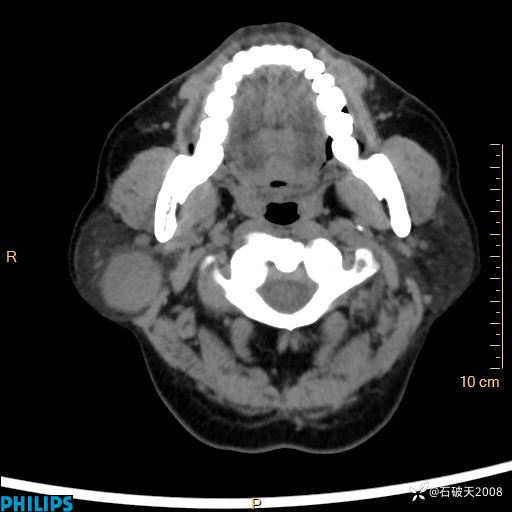

MIP